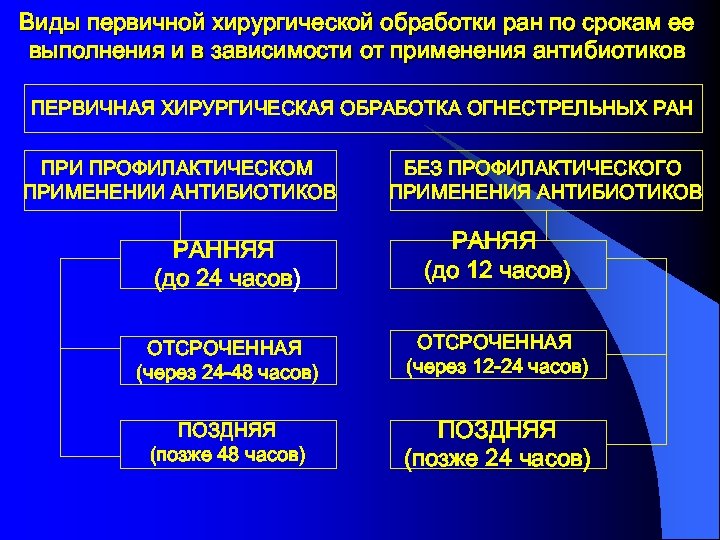

Виды первичной хирургической обработки ран по срокам ее выполнения и в зависимости от применения антибиотиков ПЕРВИЧНАЯ ХИРУРГИЧЕСКАЯ ОБРАБОТКА ОГНЕСТРЕЛЬНЫХ РАН ПРИ ПРОФИЛАКТИЧЕСКОМ ПРИМЕНЕНИИ АНТИБИОТИКОВ БЕЗ ПРОФИЛАКТИЧЕСКОГО ПРИМЕНЕНИЯ АНТИБИОТИКОВ РАННЯЯ (до 24 часов) РАНЯЯ (до 12 часов) ОТСРОЧЕННАЯ (через 24 -48 часов) ОТСРОЧЕННАЯ (через 12 -24 часов) ПОЗДНЯЯ (позже 48 часов) ПОЗДНЯЯ (позже 24 часов)

Виды первичной хирургической обработки ран по срокам ее выполнения и в зависимости от применения антибиотиков ПЕРВИЧНАЯ ХИРУРГИЧЕСКАЯ ОБРАБОТКА ОГНЕСТРЕЛЬНЫХ РАН ПРИ ПРОФИЛАКТИЧЕСКОМ ПРИМЕНЕНИИ АНТИБИОТИКОВ БЕЗ ПРОФИЛАКТИЧЕСКОГО ПРИМЕНЕНИЯ АНТИБИОТИКОВ РАННЯЯ (до 24 часов) РАНЯЯ (до 12 часов) ОТСРОЧЕННАЯ (через 24 -48 часов) ОТСРОЧЕННАЯ (через 12 -24 часов) ПОЗДНЯЯ (позже 48 часов) ПОЗДНЯЯ (позже 24 часов)